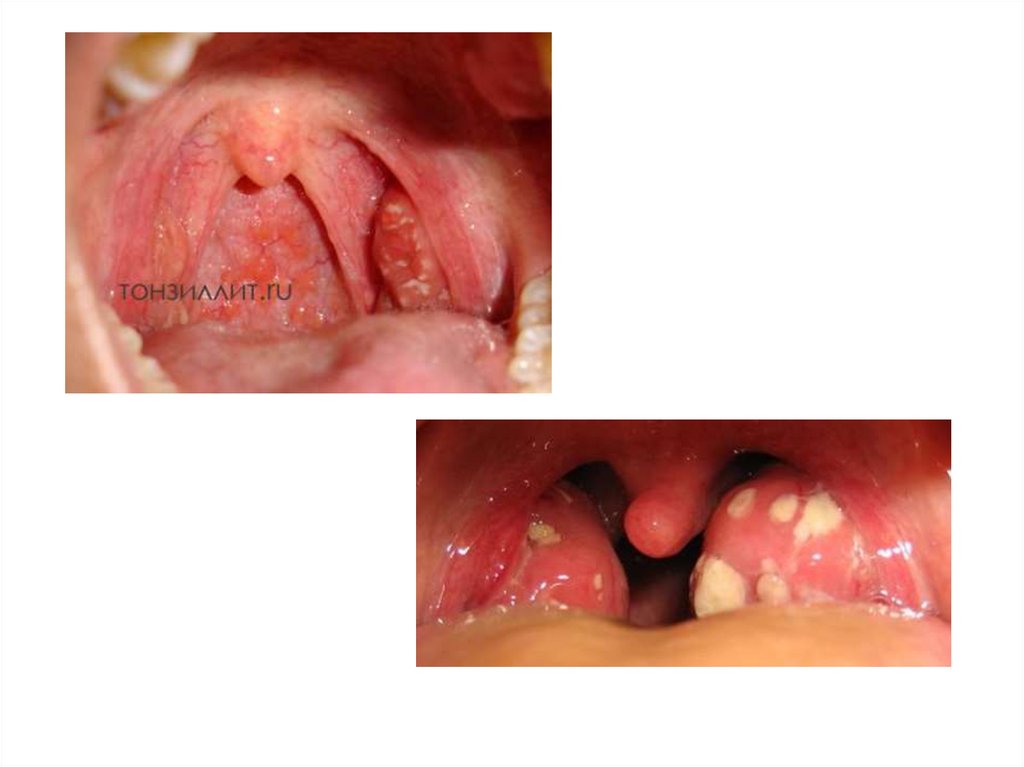

Фарингоскопические признаки

ангины Симановского-ПлаутаВенсана

• Язвенно-некротическая ангина, характерно одностороннее

поражение миндалины

• Характерными и отличительными признаками язвеннонекротической ангины являются:

• некротические изменения поверхности, как правило, одной

небной миндалины;

• формирование на поверхности миндалины эрозии, дно которой

выстлано тонкой фибринозной мембраной;

• под фибринозной мембраной скрывается участок некроза тканей